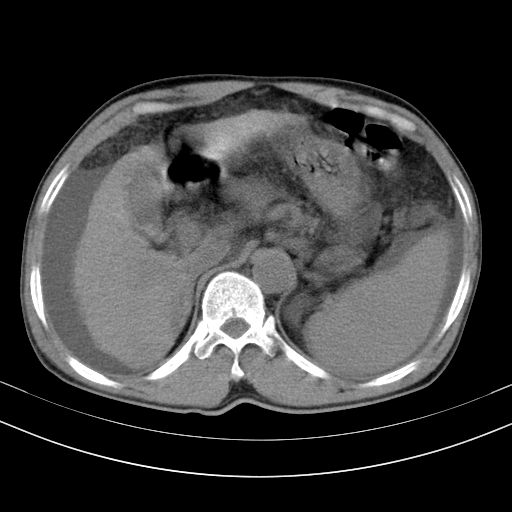

以下是引用随光逐影在2010-2-28 10:23:00的发言:[br]1)考虑肝癌;建议行ct增强扫描检查。2)肝硬化,脾大,腹水。3)慢性胆囊炎。

以下是引用dyqct在2010-2-28 16:44:00的发言:[br][quote]以下是引用随光逐影在2010-2-28 10:23:00的发言:[br]1)考虑肝癌;建议行ct增强扫描检查。2)肝硬化,脾大,腹水。3)慢性胆囊炎。